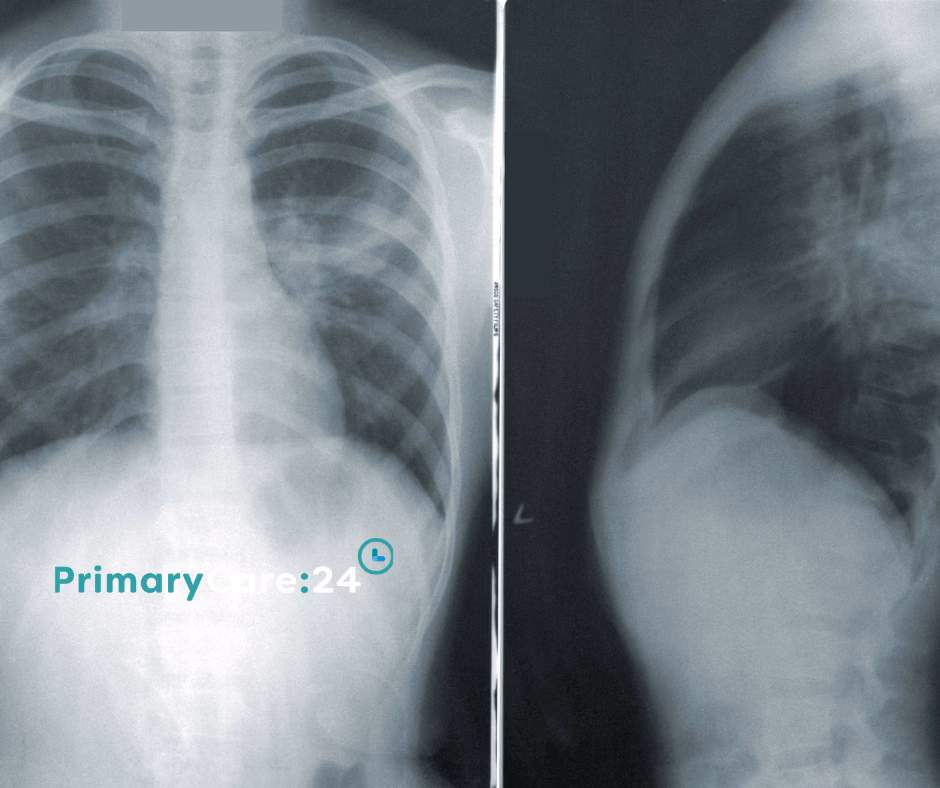

Før man kan værdsætte omfanget af 'Nul Lungebetændelse'-projektet, er det vigtigt at forstå, hvad VAP er, og hvorfor det er så farligt. Når en patient lægges i respirator, føres et rør (en endotrakealtube) ned gennem luftrøret. Dette rør er livsnødvendigt, men det udgør også en direkte adgangsvej for bakterier fra munden og svælget til lungerne. Patienternes svækkede immunforsvar og manglende evne til at hoste effektivt øger risikoen markant. En VAP-infektion forlænger patientens ophold på intensivafdelingen, øger behovet for antibiotika (hvilket kan føre til resistens), medfører betydelige lidelser og forøger dødeligheden dramatisk. Det er en alvorlig og omkostningstung komplikation, som sundhedsvæsenet aktivt søger at bekæmpe.